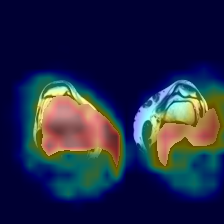

5.3.1 Coherence Score of Annotations

We chose the Fusion_Gate method for our application-grounded evaluation because it achieved the highest scores, albeit modest, in our functionally-grounded evaluation. Figure 7 presents all five distal myopathy cases side by side with their reference masks and the corresponding Fusion_Gate saliency maps, providing a direct visual comparison of true pathology versus model-identified regions. After converting each HCP’s annotations into binary masks, we computed the coherence between those masks and the Fusion_Gate saliency maps (Table 7). The large spread in RMA and RRA values demonstrates that even minor discrepancies in the ground truth mask can dramatically alter coherence scores, emphasizing the critical need for highly accurate, consensus ground truth annotations when using coherence as an interpretability metric. We then assessed each HCP’s overall annotation accuracy by RMA¯\overline{\mathrm{RMA}}over¯ start_ARG roman_RMA end_ARG and RRA¯\overline{\mathrm{RRA}}over¯ start_ARG roman_RRA end_ARG against the reference masks (first column of Table 8). RMA¯\overline{\mathrm{RMA}}over¯ start_ARG roman_RMA end_ARG indicates that HCPs reliably identify the general signal alteration regions, but their consistently lower RRA¯\overline{\mathrm{RRA}}over¯ start_ARG roman_RRA end_ARG confirms they lack the fine-grained precision of the expert in isolating the most critical subregions. Notably, when we compare these human baselines to the Fusion_Gate’s mean coherence scores (Table 5), the method’s RRA¯\overline{\mathrm{RRA}}over¯ start_ARG roman_RRA end_ARG surpasses that of all but two HCPs. In other words, the attention mechanism could faithfully highlights the single most important pixel than most individual annotators. Lastly, the comparatively low RMA¯\overline{\mathrm{RMA}}over¯ start_ARG roman_RMA end_ARG and RRA¯\overline{\mathrm{RRA}}over¯ start_ARG roman_RRA end_ARG values in the second column of Table 8, which quantify how well the Fusion_Gate saliency maps align with each HCP’s own mask, reveal that even our best interpretability method still falls short of expert-level delineation. In other words, although attention-based saliency can highlight broadly relevant regions, it does not yet match the clinical precision of HCPs’ annotators. This gap underscores that, despite promising advances, more work is needed before automated explanations can achieve the same fidelity as experienced radiologists.

Refer to caption

(a) Image 1

(b) Ground truth Mask 1

(c) Saliency Map 1

(d) Image 2

(e) Ground truth Mask 2

(f) Saliency Map 2

(g) Image 3

(h) Ground truth Mask 3

(i) Saliency Map 3

(j) Image 4

(k) Ground truth Mask 4

(l) Saliency Map 4

(m) Image 5

(n) Ground truth Mask 5

(o) Saliency Map 5

Figure 7: Image instances of the distal myopathy dataset with their corresponding reference masks and saliency maps.